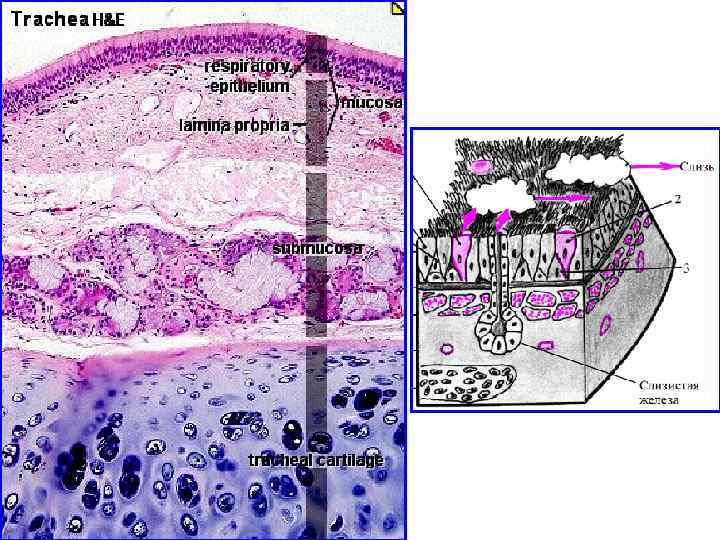

Трахея является органом слоистого типа, состоит из 4 -х оболочек: слизистой, подслизистой, хрящевой и адвентициальной. фиброзно-

Слизистая оболочка состоит из многорядного реснитчатого эпителия и собственной пластинки.

Эпителий трахеи содержит реснитчатые, бокаловидные, вставочные и эндокринные клетки. Реснитчатые клетки имеют реснички, колеблющиеся против движения вдыхаемого воздуха. Они удаляют микроорганизмы и инородные частицы. Бокаловидные клетки секретируют муцины - слизь, которая склеивает инородные тела, бактерии и облегчает их выделение. Микроворсинчатые клетки являются хеморецепторными. Базальные или вставочные клетки играют роль камбия.

Бокаловидные реснитчатые клетки образуют слизисто-реснитчатый (мукоцилиарный) конвейер. В норме соотношение бокаловидных и реснитчатых клеток равно 1/10. В этом случае осуществляется оптимально работа конвейера: реснички успевают эвакуировать всю слизь, образованную бокаловидными клетками. При курении, воспалении трахеи соотношение изменяется в пользу бокаловидных клеток. Образуется избыток слизи, который не успевает удаляться, теряет свои бактерицидные свойства и инфицируется, формируется трахеит курильщика.